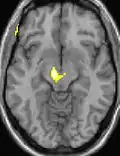

| Voxel-based morphometry shows brain area structural differences. | ||

Positron emission tomography (PET) scans indicate the brain areas which are activated during attack only, compared to pain free periods. These pictures show brain areas that are active during pain in yellow/orange color (called "pain matrix"). The area in the center (in all three views) is activated only during cluster headaches. The bottom row voxel-based morphometry shows structural brain differences between individuals with and without CH; only a portion of the hypothalamus is different.[36]